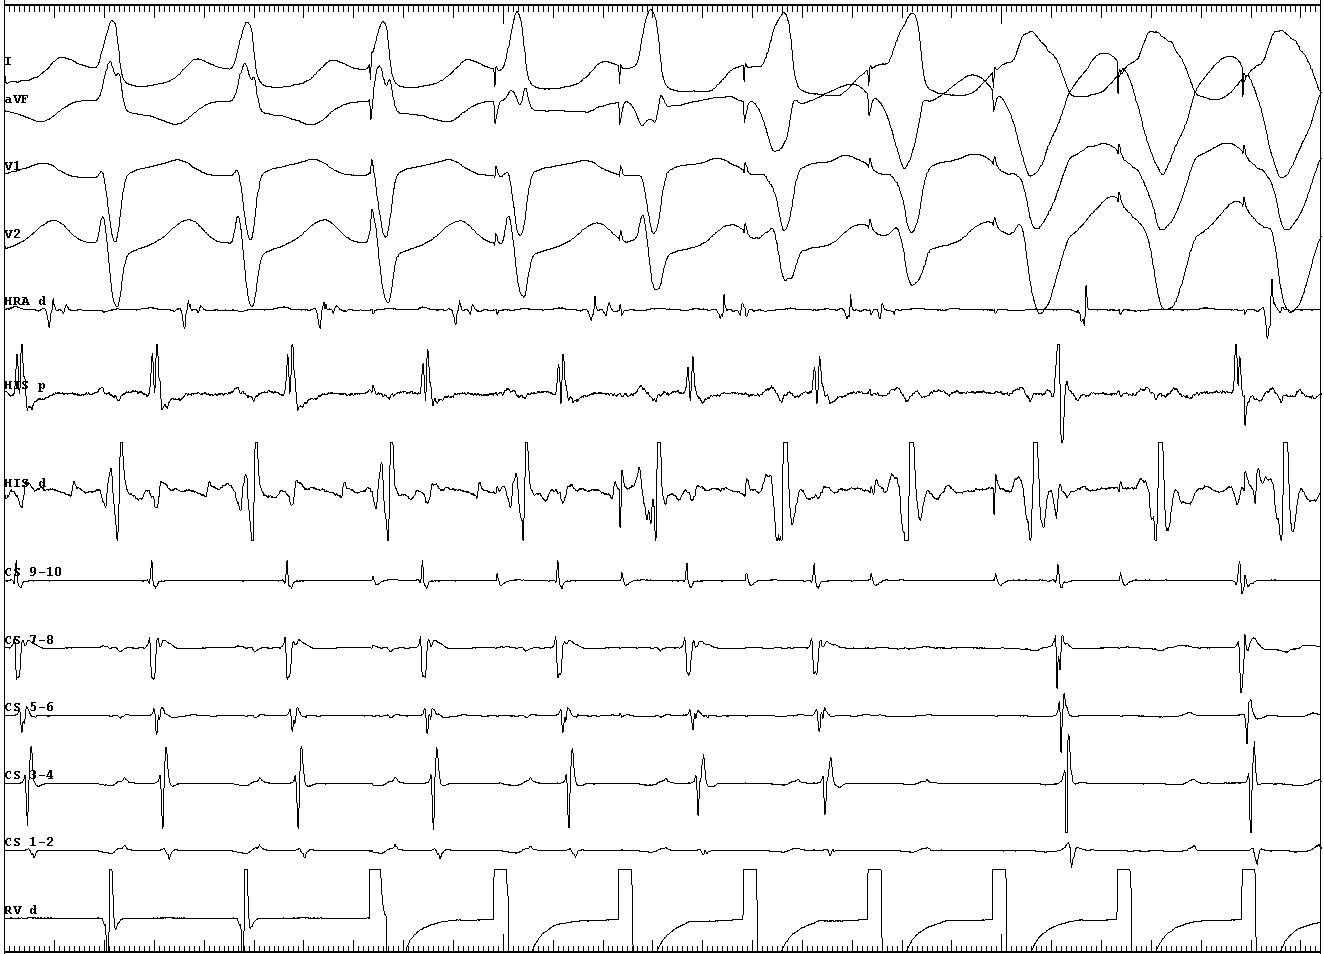

Also useful in eccentric VA conduction

vav_llap.JPG

Eccentric conduction

vav_rt_anterolat_ap.JPG

AVRT or AVNRT ? - cPPI-TCL

vav_avrt.jpg